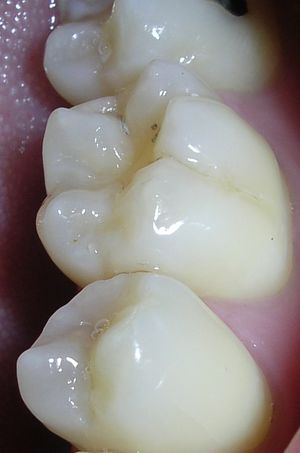

| Destruction of a tooth by cervical decay from dental caries | |

هو تخرب يصيب نسج السن الصلبة بدءاً من طبقة الميناء enamel ثم يصل إلى طبقة العاج محدثاً حفرة قد تزداد اتساعاً وعمقاً لتصل إلى اللب الذي يحتوي الأوعية الدموية والأعصاب.

حدوث التسوس وتطوره

تقوم الحموض الناتجة من عملية تخمر السكاكر بحل العناصر المعدنية والعضوية التي تدخل في تركيب ميناء السن فتبدو المنطقة بيضاء طبشورية وذات ملمس خشن. ولدى تزايد إنتاج الحموض وعدم تطبيق الفلوريد الموضعي على الأسنان الذي يقوم عادة بإيقاف تطور التسوس، يتهدم الميناء وتصل الإصابة إلى العاج مشكلة حفرة التسوس التي يمكن ملاحظتها سريرياً ويبدأ الإحساس بالألم لدى التعرض إلى مؤثرات خارجية من سخونة وبرودة أو الضغط أثناء المضغ. عند إهمال معالجة التسوس في هذه المرحلة يزداد التخرب وتصل الإصابة إلى لب السن الذي يصاب بالالتهاب وترافقه موجات حادة من الألم وخاصة في أثناء الليل. إن عدم تطبيق المعالجة الملائمة في هذه المرحلة يؤدي إلى تموت اللب وإصابته بالتعفن وتتكون الخراجات الحادة والمزمنة والآفات الذروية التي تنتهي بقلع السن المصابة.